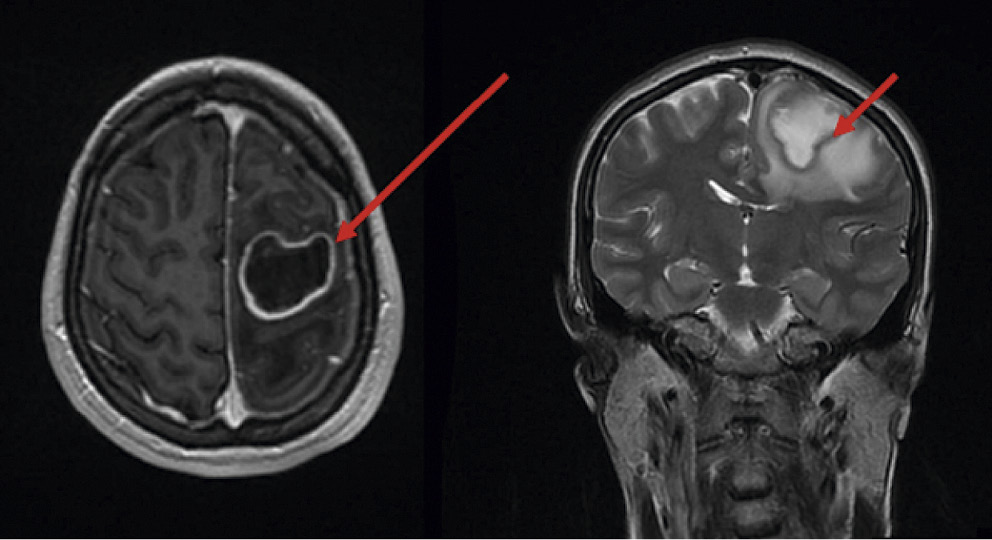

Пациентка была обследована по поводу диагноза «Острое нарушение мозгового кровообращения по недифференцированному типу». По данным магнитно-резонансной томографии (МРТ) головного мозга у пациентки были выявлены признаки объемного образования в левой теменной доле с «масс-эффектом», что, по мнению врачей, соответствовало типичной картине опухоли (рис. 8).

Рис. 8. Результаты магнитно-резонансной томографии пациентки

Fig. 8. A patient's MRI findings

Однако после получения положительных результатов серологических тестов для выявления антител к T. pallidum и спинномозговой (цереброспинальной) жидкости оказалось, что под опухолью головного мозга маскировалась сифилитическая гумма (нейросифилис поздний). После проведенного специфического противосифилитического лечения у пациентки, по данным мультиспиральной компьютерной томографии (МСКТ), отмечалась положительная динамика: уменьшение отека вещества головного мозга и выраженности дислокации срединных структур (рис. 9).

Данный клинический случай наглядно демонстрирует, насколько сложна дифференциальная диагностика позднего сифилиса (нейросифилиса), который может успешно маскироваться под другие заболевания.